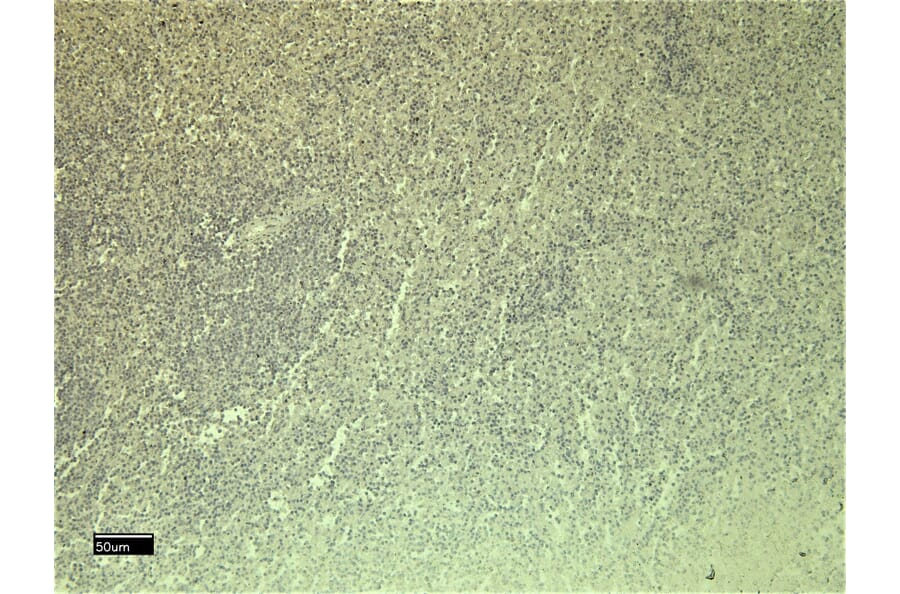

C5a-R expression in Human Spleen analyzed by immunohistochemistry. Tissue was paraffin-embedded, and antigen retrieval was achieved by heating in citrate buffer, pH 6. Staining was performed with Anti-C5a-R Antibody (A286040) at 6µg/ml and revealed with horseradish peroxidase (HRP).

Negative control for C5a-R expression in Human Spleen analyzed by immunohistochemistry. Tissue was paraffin-embedded, and staining procedure was performed in the absence of primary antibody.